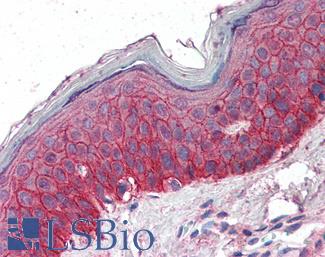

EGFR

Anti-EGFR antibody IHC of human skin. Immunohistochemistry of formalin-fixed, paraffin-embedded tissue after heat-induced antigen retrieval. Antibody LS-B2914 concentration 5 ug/ml.